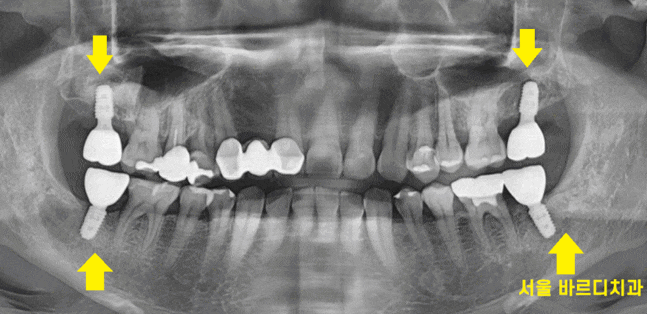

명일동 치과를 처음 방문하셨을 때 사진입니다.

보시는 것처럼

위, 아래

오른쪽, 왼쪽

사이좋게 양쪽 맨 끝 어금니를

상실하신 채 내원하셨어요.

총 4개 치아가 없으셨습니다.